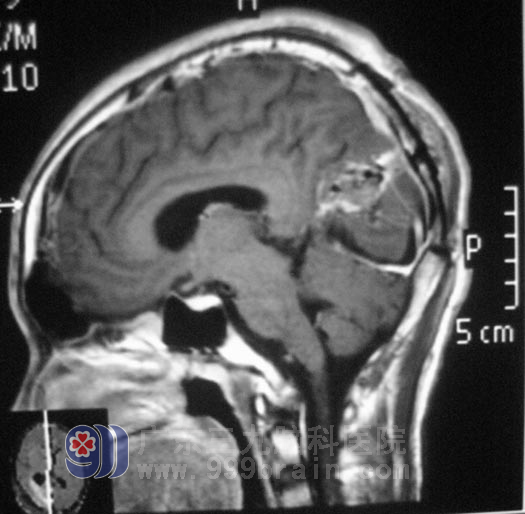

慕名来到广东三九脑科医院,综合神经外科 鲁明主任经过检查后,初步考虑为星形细胞瘤。2月24日,鲁明主任主刀在全麻下行右侧枕叶占位性病变切除术,术中显微镜下见粉红色肿瘤,质地较韧,血供丰富,肿瘤主要位于枕叶,内近大脑镰,予肿瘤全切。术后儿子的精神症状逐渐好转,头痛头晕症状明显消失,未再出现呕吐。全家人如释负重,还有些隐隐担心。术后病理结果为:肥胖性星形细胞瘤。